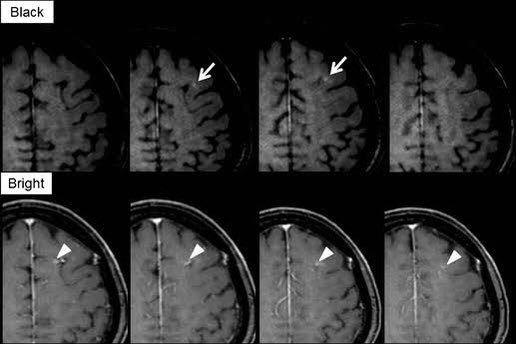

造影MRI検査で脳転移を診断する際に、T1 MPRAGEで読影する施設多いかと思います。

読影の際に、転移なのか?血管なのか?連続性を見て確認すると思うのですが、この論文の方法であれば、血管がBlack Bloodになり読影時間を短縮できそうです。